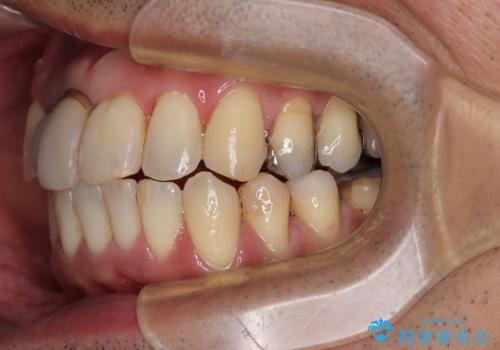

隠れている前歯 インビザライン矯正治療と前歯のセラミック治療

- 隠れるほどに内側に転位しいてる前歯を気にして来院された患者様です。

仕事柄海外出張が多いとのことで、インビザラインにて矯正治療を行うこととしました。

矯正治療後は、前歯や下顎の奥歯など、むし歯治療途中の歯をオールセラミッククラウンにて補綴治療を行うこととしました。

内側に転位していた前歯は、矯正治療では治しきることができませんでしたが、幸いにもオールセラミッククラウンに置き換える予定であったため、希望通りの仕上がりとなりました。